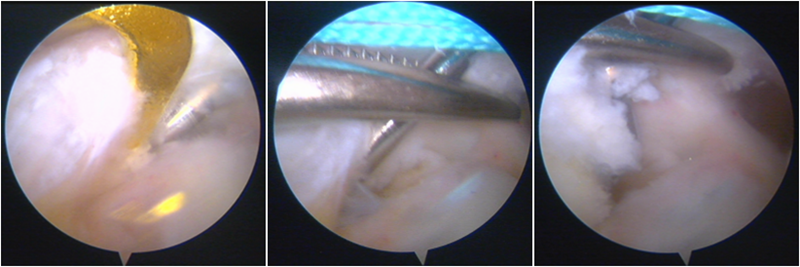

股骨侧保残骨道建立

股骨侧骨道建立,椭圆形扩孔保残9mm

韧带导入过程